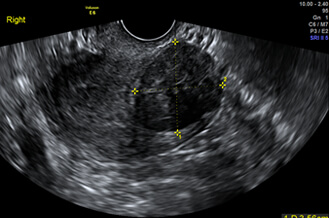

正常子宮

超音波探頭伸入陰道後,可以縮短探頭與子宮和卵巢的距離,看到子宮和卵巢更多的細節。檢查約2~3分鐘內可完成。